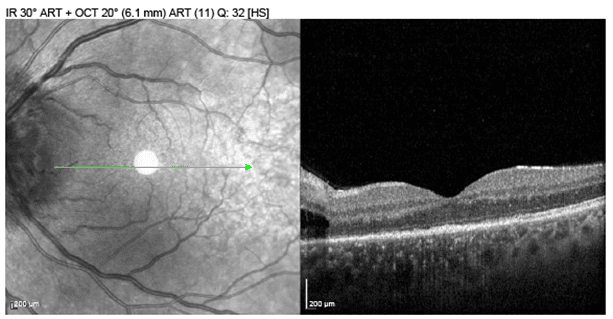

LatestPhoto Essay – A Spiral Illusion: An Atypical Presentation of Schlaegel Lines

This case describes an unusual spiral pattern of Schlaegel lines in a patient with inactive multifocal choroiditis. Although most often associated with...

Photo Essay – A Spiral Illusion: An Atypical Presentation of Schlaegel Lines

by Theresa Jay, OD, FAAO, Steve Njeru, OD, MS, FAAO and Melissa Chen, OD | Aug 19, 2025

This case describes an unusual spiral pattern of Schlaegel lines in a patient with inactive multifocal choroiditis. Although most often associated with...

Photo Essay – A Spiral Illusion: An Atypical Presentation of Schlaegel Lines

by Theresa Jay, OD, FAAO, Steve Njeru, OD, MS, FAAO and Melissa Chen, OD | Aug 19, 2025 | Photo Essay, Retina, Volume 3, Issue 3 | 0 |

This case describes an unusual spiral pattern of Schlaegel lines in a patient with inactive multifocal choroiditis. Although most often associated with...